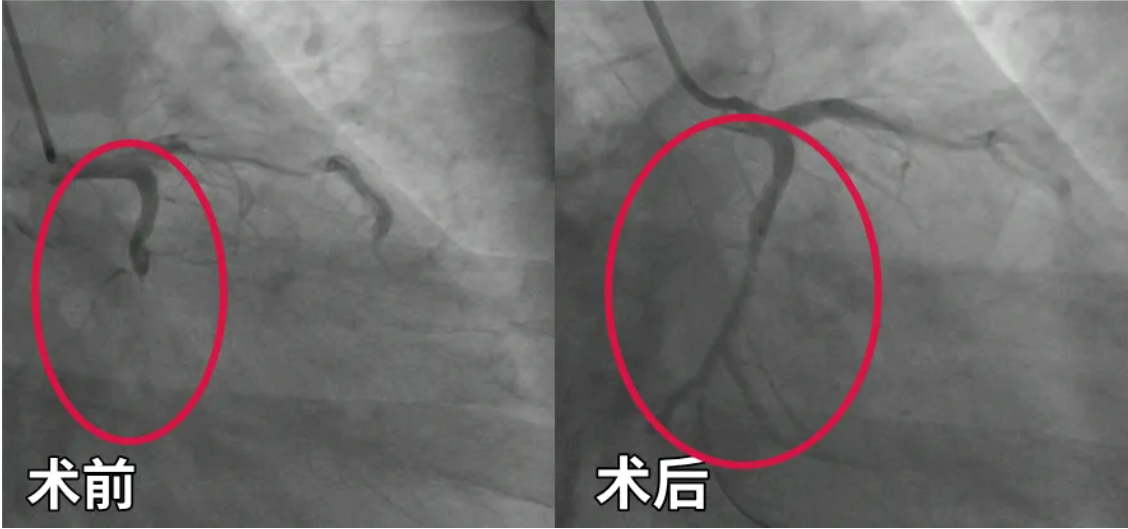

阿华术前术后血管对比

红圈内的血管术后得到明显疏通▼